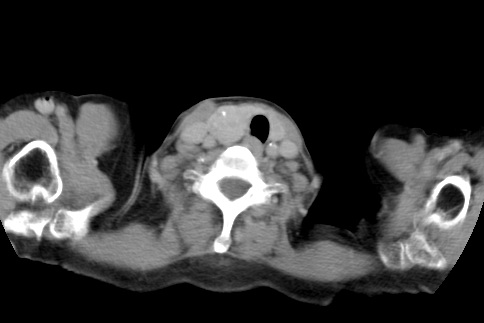

标题: CT23982:女67岁,胸部扫描时发现,甲状腺瘤? [打印本页]

标题: CT23982:女67岁,胸部扫描时发现,甲状腺瘤?

右侧甲状腺腺瘤!支持!不排除甲状腺癌可能!建议手术切除!

右侧甲状腺占位性病变,性质待定(甲状腺腺瘤?);建议:必要时行进一步检查。

右侧甲状腺占位性病变,性质待定(甲状腺腺瘤?);

右侧甲状腺占位性病变,性质待定(甲状腺腺瘤?);建议穿刺活检。

右侧甲状腺占位性病变,甲状腺腺瘤可能,建议穿刺活检。